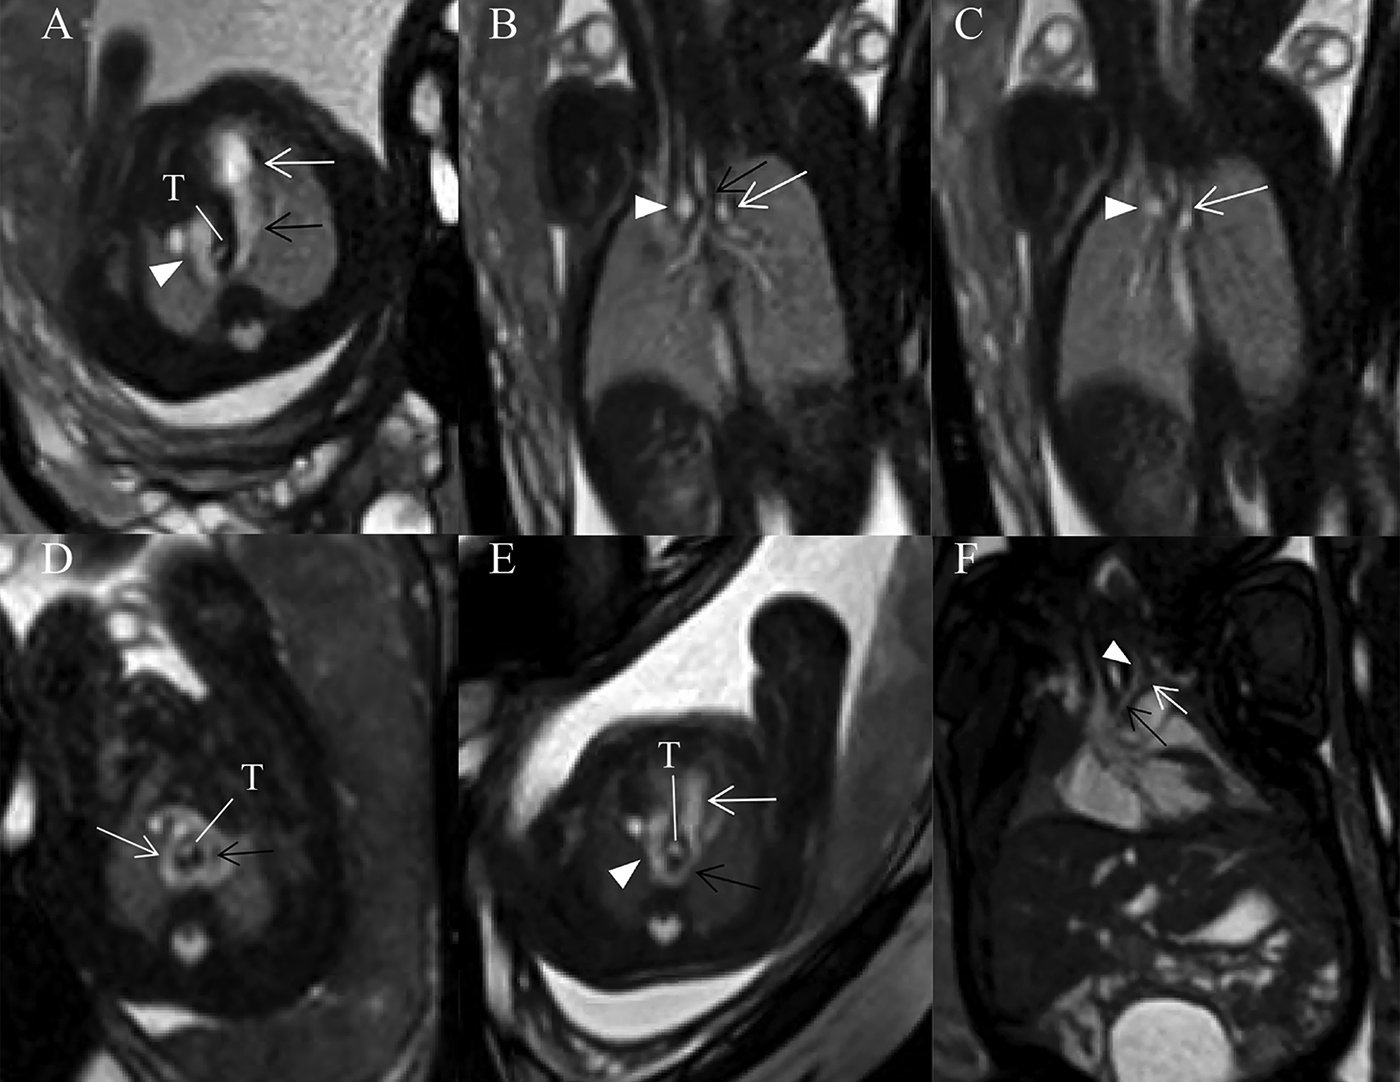

This retrospective study included 390 pregnant women (130 carrying fetuses with CVR, 260 carrying healthy fetuses). The GA of these fetuses at time of fetal MRI ranged from 22 to 37 weeks (mean, 26.3 weeks) both in normal control and CVR groups. Fetal CVR included RAA with ALSA and left DA (Figures 3A–C) (n = 93), DAA (Figure 3D) (n = 29), and RAA with mirror-image branching and RLDA (Figures 3E,F) (n = 8). 29 confirmed cases of DAA included 19 cases of right dominant arch type, 5 cases of balanced arch type and 5 cases of left dominant arch type. Except for one case of bilateral DA, the remaining DAA fetuses were all with left-sided DA.

Figure 3

(A–F) Fetuses with subtype CVRs. (A) A 27 weeks’ gestation fetus with RAA with ALSA and left DA. Fetal cardiovascular magnetic resonance SSFP sequence transverse view of AA image showed right aortic arch (white arrowhead), left-sided DA (black open arrow) and main pulmonary artery (white open arrow) forming a U-shaped loop around the fetal trachea (T). (B) Same fetus with (A). Fetal cardiovascular magnetic resonance SSFP sequence coronary view image showed the trachea stenosis (black open arrow), right aortic arch (white arrowhead) and aberrant left subclavian artery (white open arrow). (C) Same fetus as (A). Fetal cardiovascular magnetic resonance SSFP sequence coronary view image showed right aortic arch (white arrowhead) and aberrant left subclavian artery (white open arrow). (D) A 28 weeks’ gestation fetus with DAA. Fetal cardiovascular magnetic resonance SSFP sequence transverse view of AA image showed right (white open arrow, larger) and left aortic arches (black open arrow, smaller) forming an O-shaped loop around the trachea (T). (E) A 25 weeks’ gestation fetus with RAA with mirror-image branching and RLDA. Fetal cardiovascular magnetic resonance SSFP sequence transverse view of AA image showed retroesophageal ductus (black open arrow), right aortic arch (white arrowhead), and main pulmonary artery (white open arrow). A U-shaped loop around the fetal trachea (T). (F) A 37 weeks’ gestation fetus with RAA with mirror-image branching and RLDA. Fetal cardiac magnetic resonance SSFP coronal view image showed left innominate artery (black arrow), left common carotid artery (white arrowhead), and left subclavian artery (white open arrow).

As for MRI diagnosis of fetal vascular rings, when a U-shaped vascular loop was formed around the trachea, with persistent RAA, left descending aorta, and left DA, with persistent RAA, left descending aorta, and left DA, RAA with ALSA and left DA was diagnosed; when the ascending aorta was divided into the right and left AAs surrounding the trachea and esophagus with an O-shape and converge into the descending aorta in the transverse AA view, DAA was diagnosed; when a U-shaped vascular loop was formed with left DA extending from left pulmonary artery through the posterior side of the esophagus to left proximal descending aorta in the transverse view, but there is no aberrant left subclavian artery in the coronal view, RAA with mirror-image branching and RLDA was diagnosed.